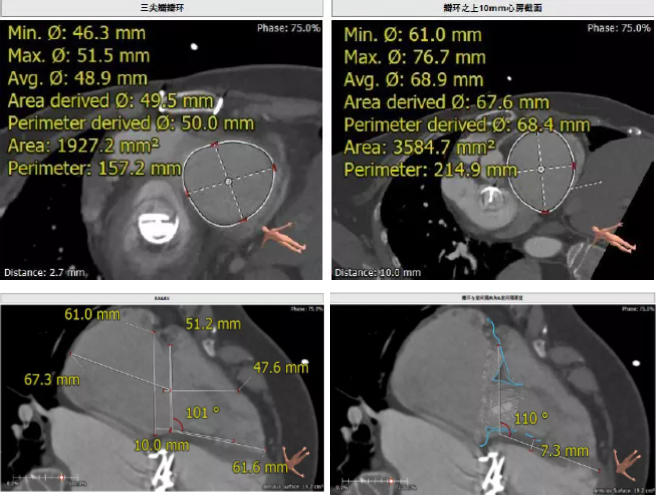

術(shù)前CT評(píng)估

患者為68歲女性,14年前因“反復(fù)感冒、氣促”,檢查發(fā)現(xiàn)心臟瓣膜病,接受了“二尖瓣機(jī)械瓣置換術(shù)”。約5年前出現(xiàn)雙下肢水腫,活動(dòng)后心累氣緊,心臟彩超提示:三尖瓣返流。近年來(lái)三尖瓣返流逐漸加重并伴有輕微黃疸、雙下肢水腫,雖長(zhǎng)期服用利尿劑治療,但效果欠佳。郭惠明教授團(tuán)隊(duì)結(jié)合病史、超聲及CT評(píng)估,考慮患者瓣膜置換術(shù)后,三尖瓣重度返流,再次開胸行體外循環(huán)手術(shù)風(fēng)險(xiǎn)高,經(jīng)團(tuán)隊(duì)整體評(píng)估,決定采用最適合患者的LuX-Valve三尖瓣置換系統(tǒng)行微創(chuàng)治療,根據(jù)測(cè)量結(jié)果選擇植入JS/TTVI-28-55型號(hào)的LuX-Valve瓣膜。